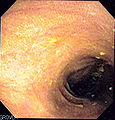

Endoscopic image

| Endoscopy | brown discolouration of the mucosa, esp. proximal colon and cecum |

- Brown pigmentation of the mucosa, especially cecum and proximal colon.[2]

- Less pigmentation distal.